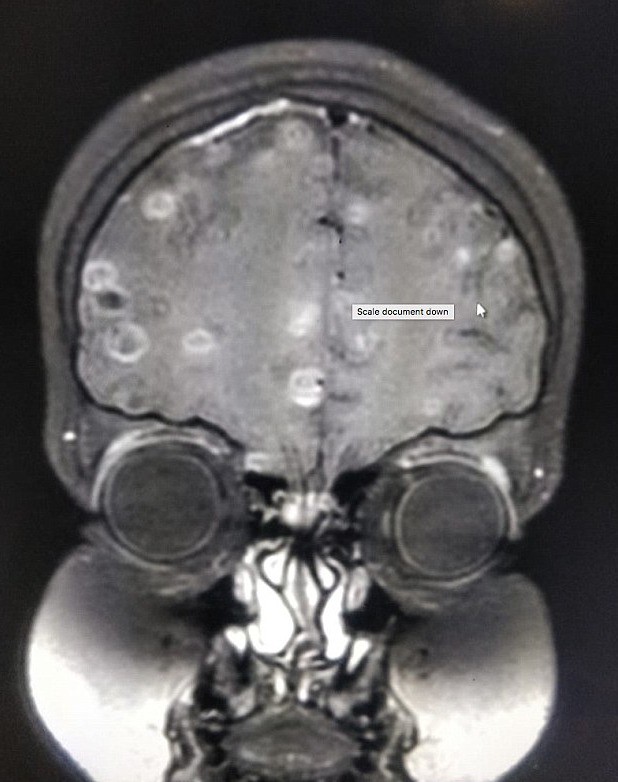

醫生決定為她再次進行腦掃瞄,才發現她是患上腦囊蟲病(Neurocysticercosis),腦部竟然有100顆絛蟲(Tapeworm)的蟲卵,處方解充血藥(decongestants)、類固醇和驅蟲劑,逐漸康復,可再次走路和上學。